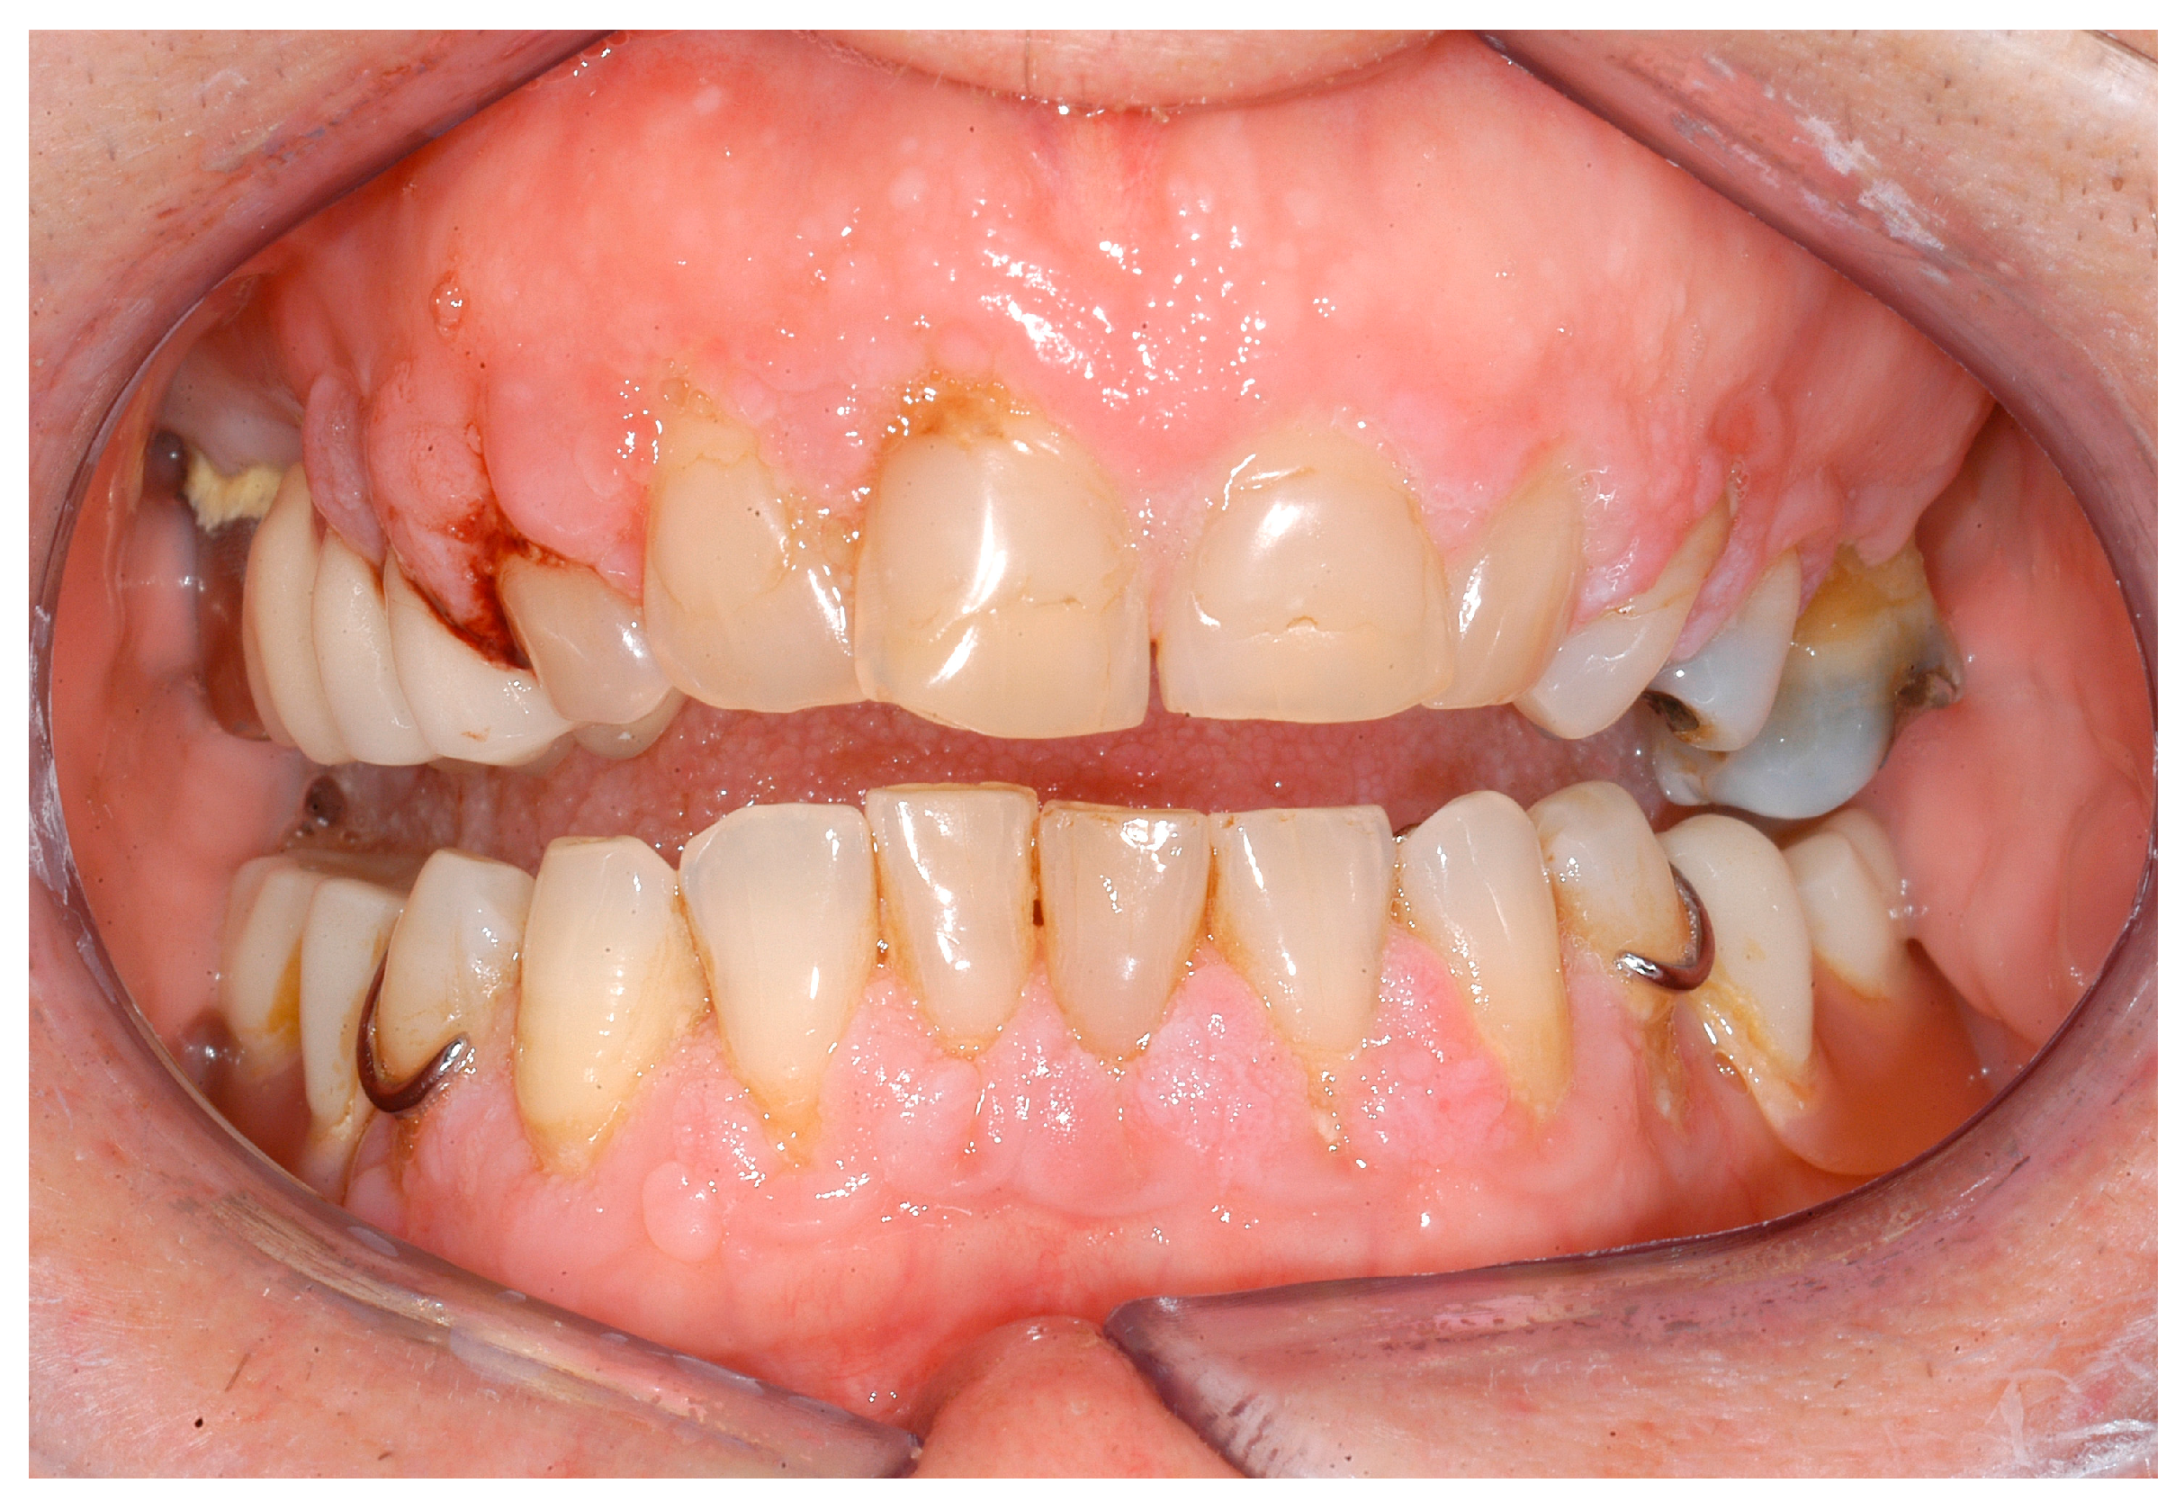

| Papillon–Lefèvre syndrome/Keratosis palmoplantar-periodontopathy syndrome Q82.8 | periodontitis | exact pathomechanism unknown [72] | CTSC, 11q14.2 [41,94] | systemic diseases and conditions that affect the periodontal attachment apparatus: diseases associated with immunologic disorders |